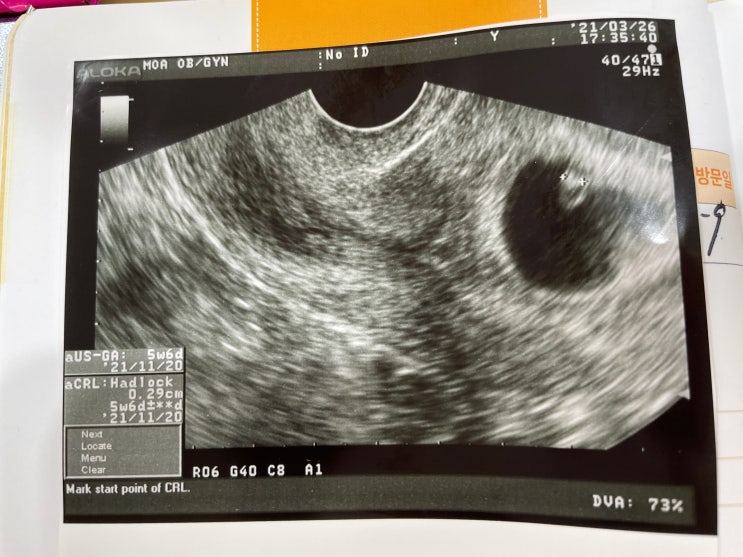

2022년 익산시 산후건강관리지원사업 신청 : )

익산보건소 4층 한방사업계에서 신청할 수 있다. (점심시간은 12시부터 1시까지!) 정신이 없어서 까먹고 있...